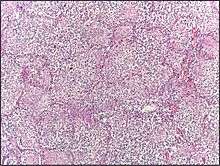

- Red hepatization or consolidation : Vascular congestion persists, with extravasation of red cells into alveolar spaces, along with increased numbers of neutrophils and fibrin. The filling of airspaces by the exudate leads to a gross appearance of solidification, or consolidation, of the alveolar parenchyma. This appearance has been likened to that of the liver, hence the term "hepatization".

- Grey hepatization : Red cells disintegrate, with persistence of the neutrophils and fibrin. The alveoli still appear consolidated, but grossly the color is paler and the cut surface is drier.